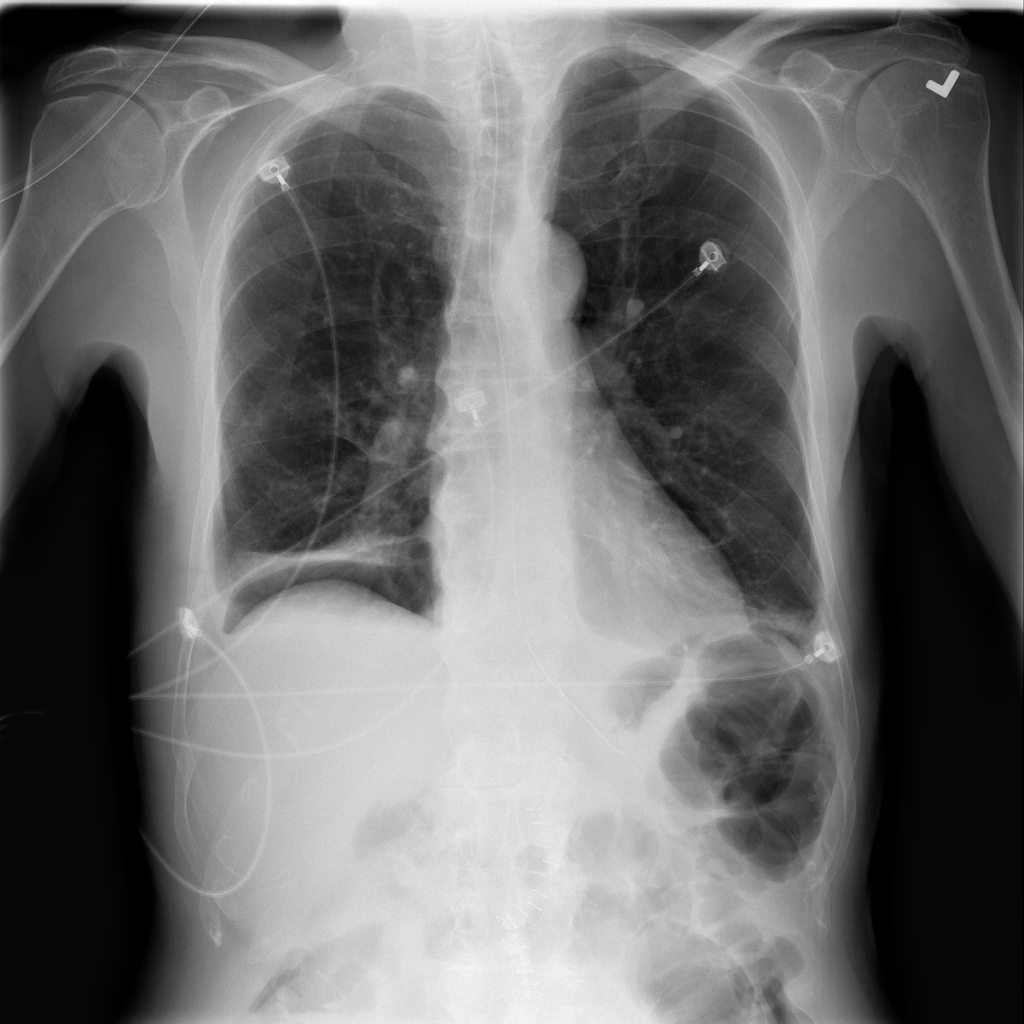

PAT-BB06 · IMG-001Atelectasis

PAT-BB06 · IMG-001

PA